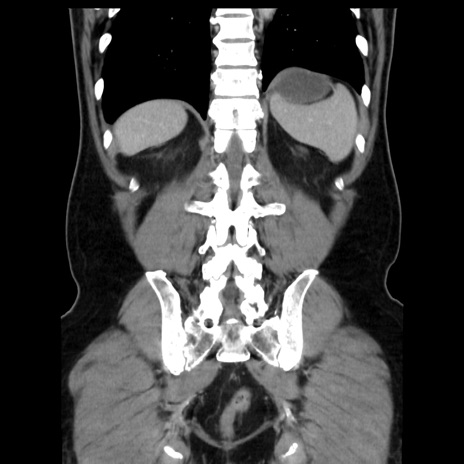

症例16(冠状断像)

【症例】 70歳代男性

【主訴】 腹痛、嘔吐

【現病歴】 約1ヶ月前より間欠的に腹痛と嘔吐あり、当院消化器内科を受診したところCTで多発する肝臓のLDAを指摘され、精査中であった。以降は消化器症状は安定していたが、2日前より嘔気と腹痛があり、同日より排便・排ガスが消失した。改善認めず、 本日、救急外来を受診した。

【既往歴】 大腸ポリープ切除後。

【身体所見】意識清明・会話良好、BT 36.3℃、BP 127/80mmHg、 P 80bpm、腹部:膨満あり、平坦・軟、上腹部正中および下腹部正中に圧痛あり、反跳痛なし、筋性防御なし。

【データ】WBC 7200、CRP 0.77